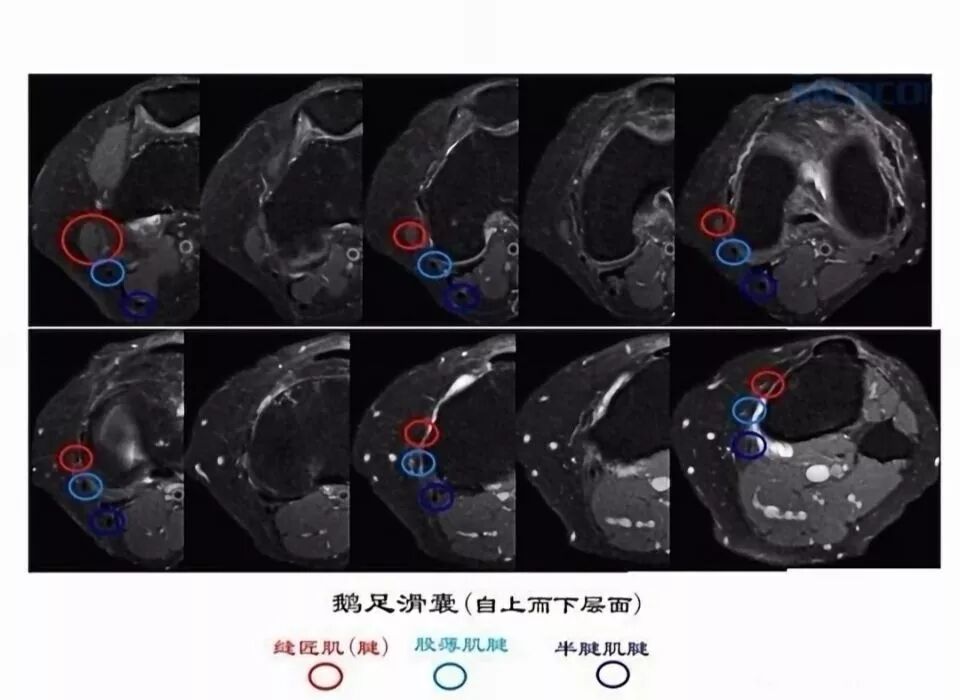

滑囊是关节囊外的囊性结构,可与关节囊相通,其作用是减少肌腱、骨和皮肤之间的摩擦。可以分为先天性滑囊和获得性滑囊。